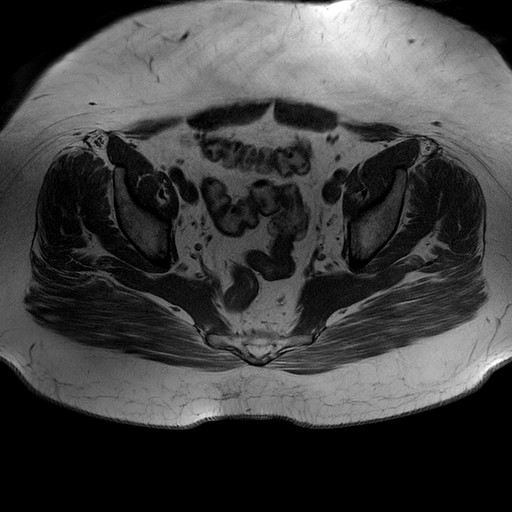

Esami: RMN BACINO

T1W_TSE

Evidenti e simmetriche alterazioni osteofitosiche in regione coxo femorale con riduzione delle rime articolari. Degenerazione completa del cercine glenoideo. Non attuali segni di versamento articolare. Non segni di edema osseo che escludono attuale algodistrofia od osteonecrosi. Lieve e simmetrica riduzione del trofismo della muscolatura glutea.